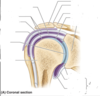

What is the glenoid fossa?

Shallow cut-like depression in a widened region of lateral scapula (socket for ball and socket shoulder joint)